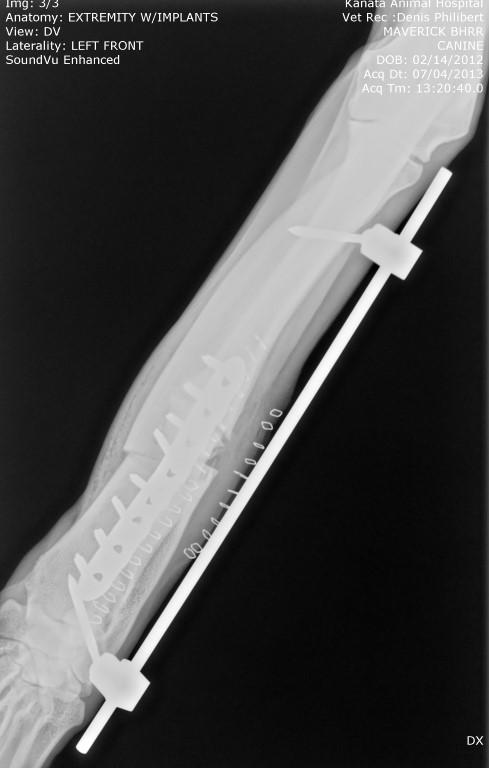

BHRR's Maverick, TTP – June 15th, 2013 & BHRR's Maverick – July 4th, post-op surgery

AND, here are his x-rays!